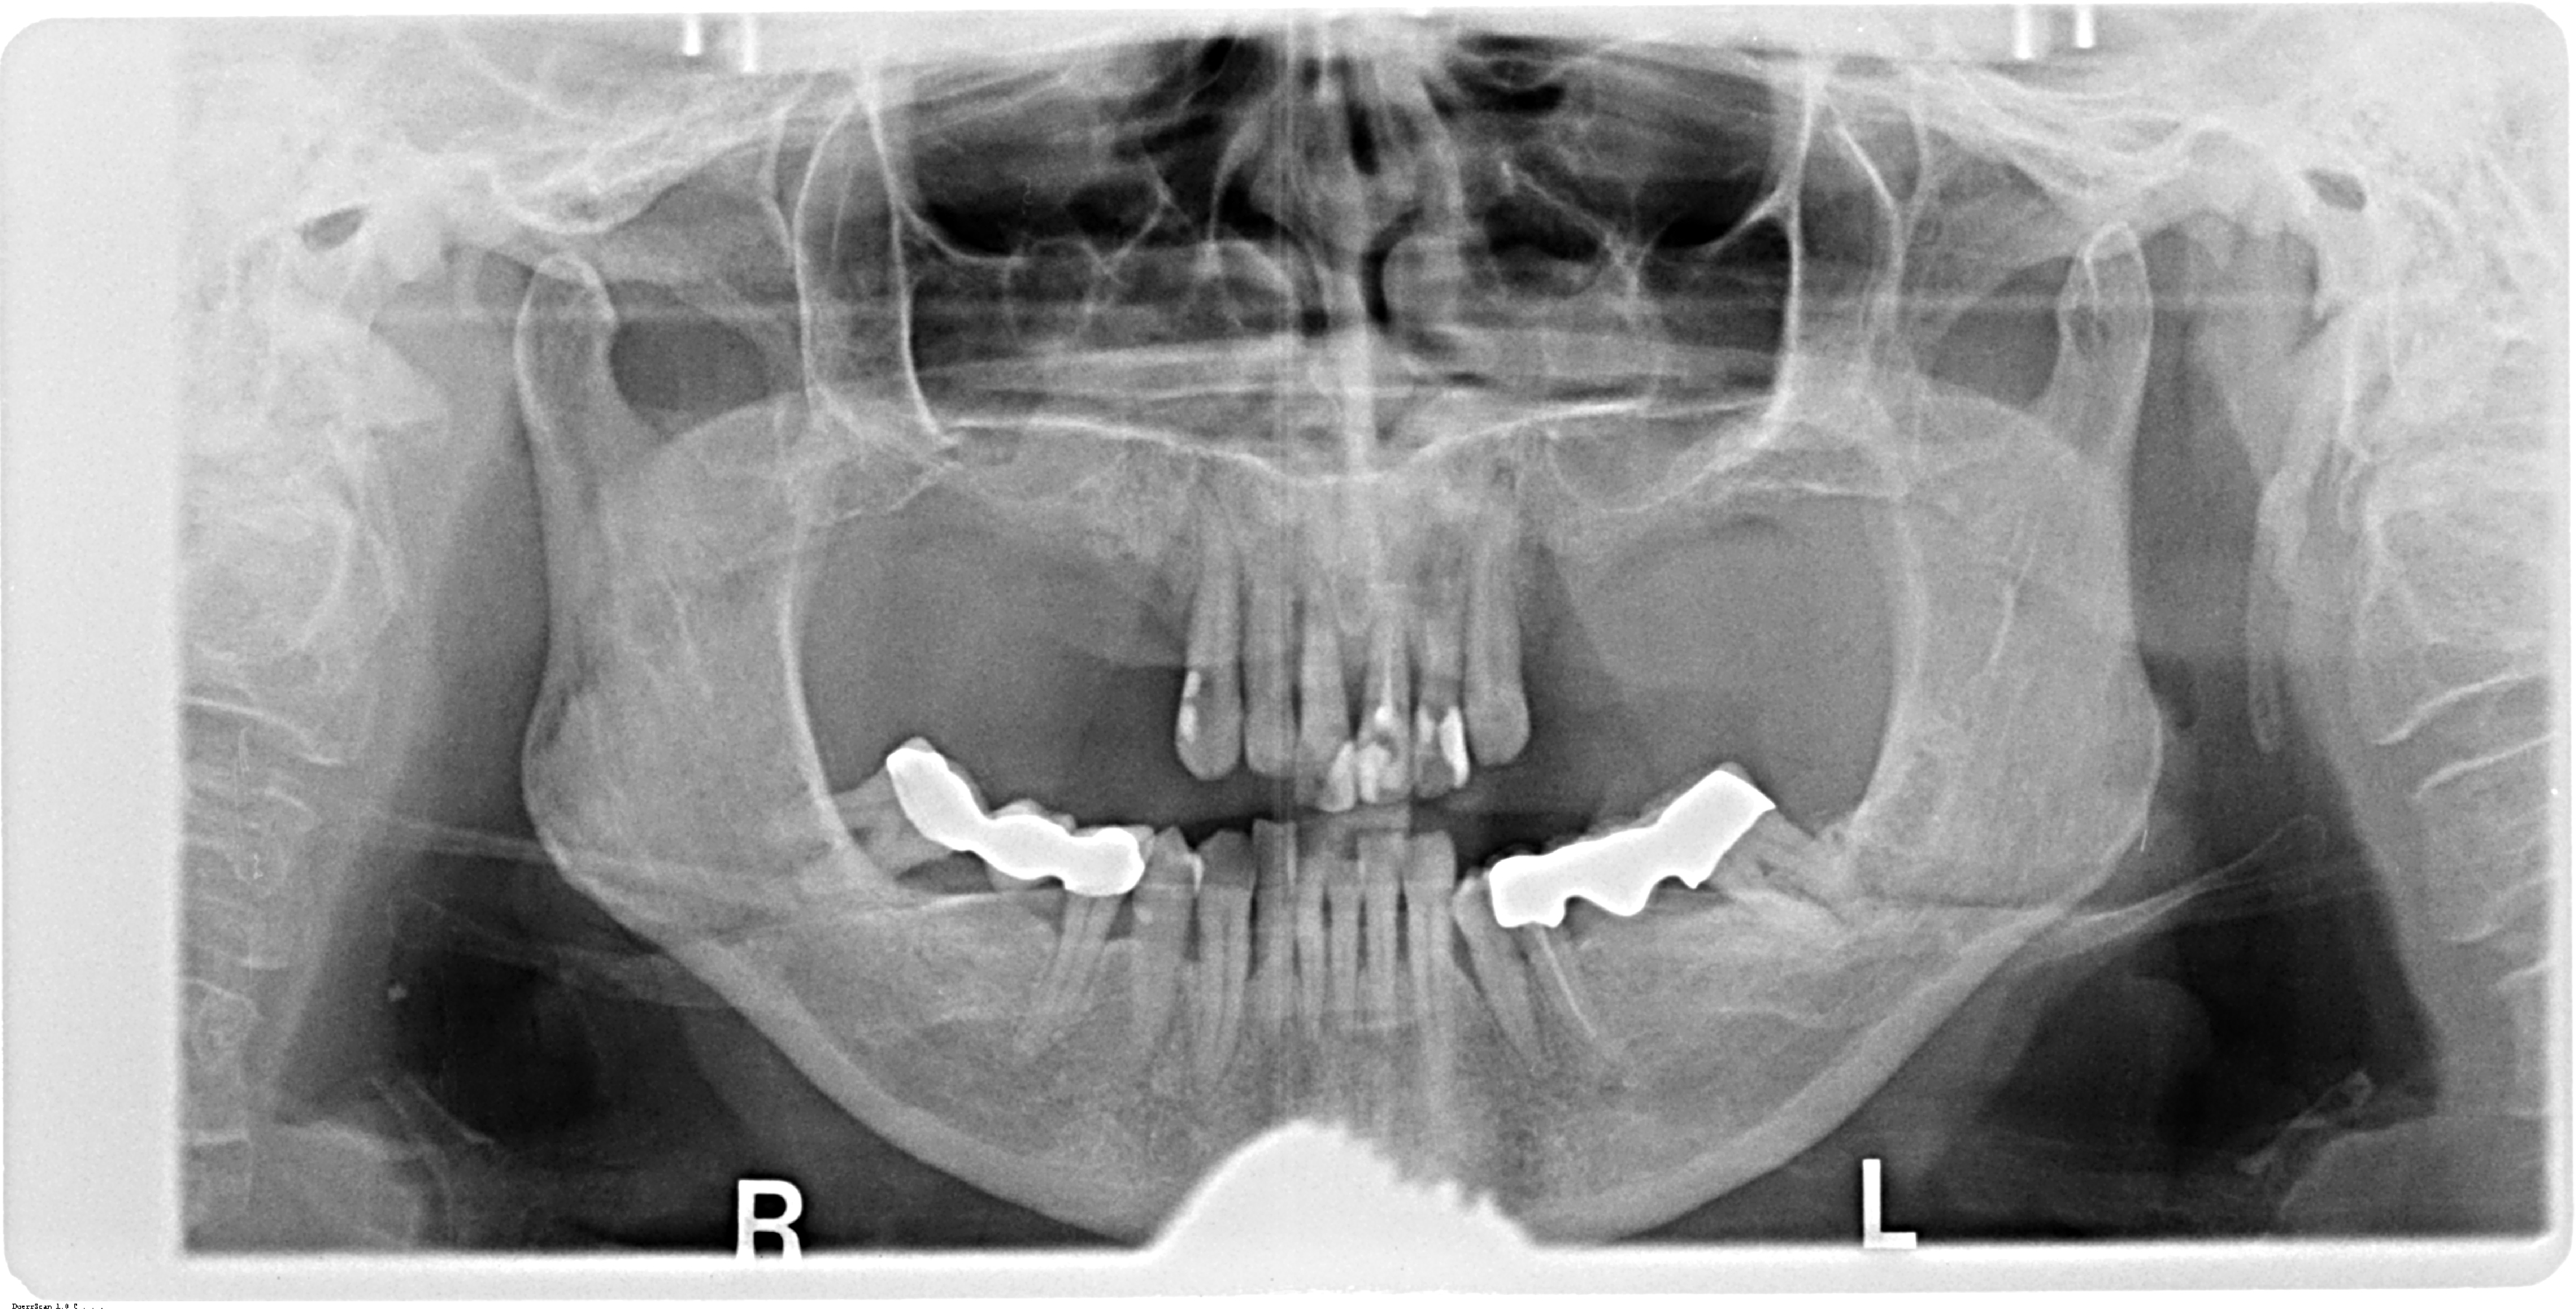

A 67-year-old female patient presented with a severely compromised anterior maxilla. Remaining teeth 13–23 showed advanced bone loss, periodontal breakdown, and a deep bite. The teeth were deemed non-restorable. The patient experienced functional limitations and significant aesthetic concern. Medical history was unremarkable.

Initial diagnostics included CBCT imaging and full-arch intraoral scanning. A digital wax-up with an increased vertical dimension of approximately 2 mm was created to simulate functional and aesthetic improvements. Fully digital implant planning was carried out, and a SMOP tooth supported guide was designed, anchored in the region of the lateral incisors.

Following the extraction of teeth 13–23, the tooth-supported guide was positioned and stabilized, allowing precise, fully guided implant surgery. Multi-Unit Abutments were inserted according to the digital plan. Immediately post-surgery, intraoral photogrammetry was performed to record the implant positions with high accuracy, eliminating the need for conventional impressions or splinting.